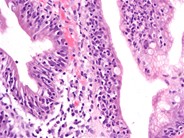

EATL Type I